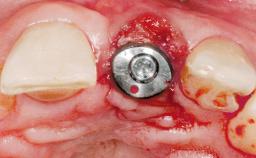

Early Placement of an Implant in a Maxillary Right Central Incisor Site

This 41-year-old female patient was referred to the clinic for the replacement of the right central incisor, since the tooth had developed a root fracture in the long axis that made extraction necessary. The healthy, non-smoking patient was first seen with the tooth still in place. A detailed Esthetic Risk Assessment was performed.The patient was worried about her dental esthetics and had high expectations for a successful treatment outcome from an esthetic point of view. The patient had a medium lip line that displayed parts of the gingiva in the anterior maxilla upon smile.

Defining Characteristics One missing tooth to be replaced by an implant-borne prosthesis

Placement Protocol Early or late implant placement

Bone Volume Deficient horizontally, allowing simultaneous augumentation

Esthetic Risk High